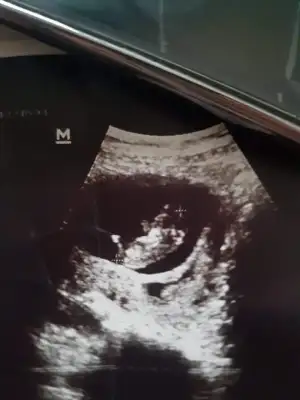

Erkek olsa göstermezmiydi kendini 😐 12.hafta da Doktor kiza benziyor emin değilim bir ay sonra belli olur dedi ama ben iki hafta sonra gittim 🤦‍♀️ bugünde dedi plasenta herşey azada toplanmış o yüzden söyleyemiyorum göstermiyor zaten dedi anlamadım

Bu haftalarda nub olayı bitiyor sanki size daha önce kız gibi demiştim dimi bu usgkaç haftalık sanki 14 gibi

Sanki boş görünüyor kız bence şimdi baktım usg 14 hafta